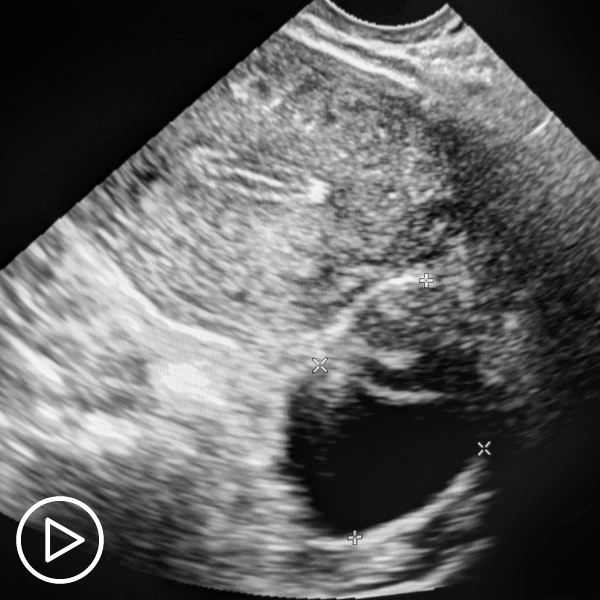

Ovarian Cysts and Uterine Fibroids: Is There a Connection to Ovarian Cancer?

https://vimeo.com/822859208 Are ovarian cysts and fibroids a concern for ovarian cancer patients? Expert Dr. Ebony Hoskins shares her perspective about fibroids and cysts, what she looks for in patients, and her advice…